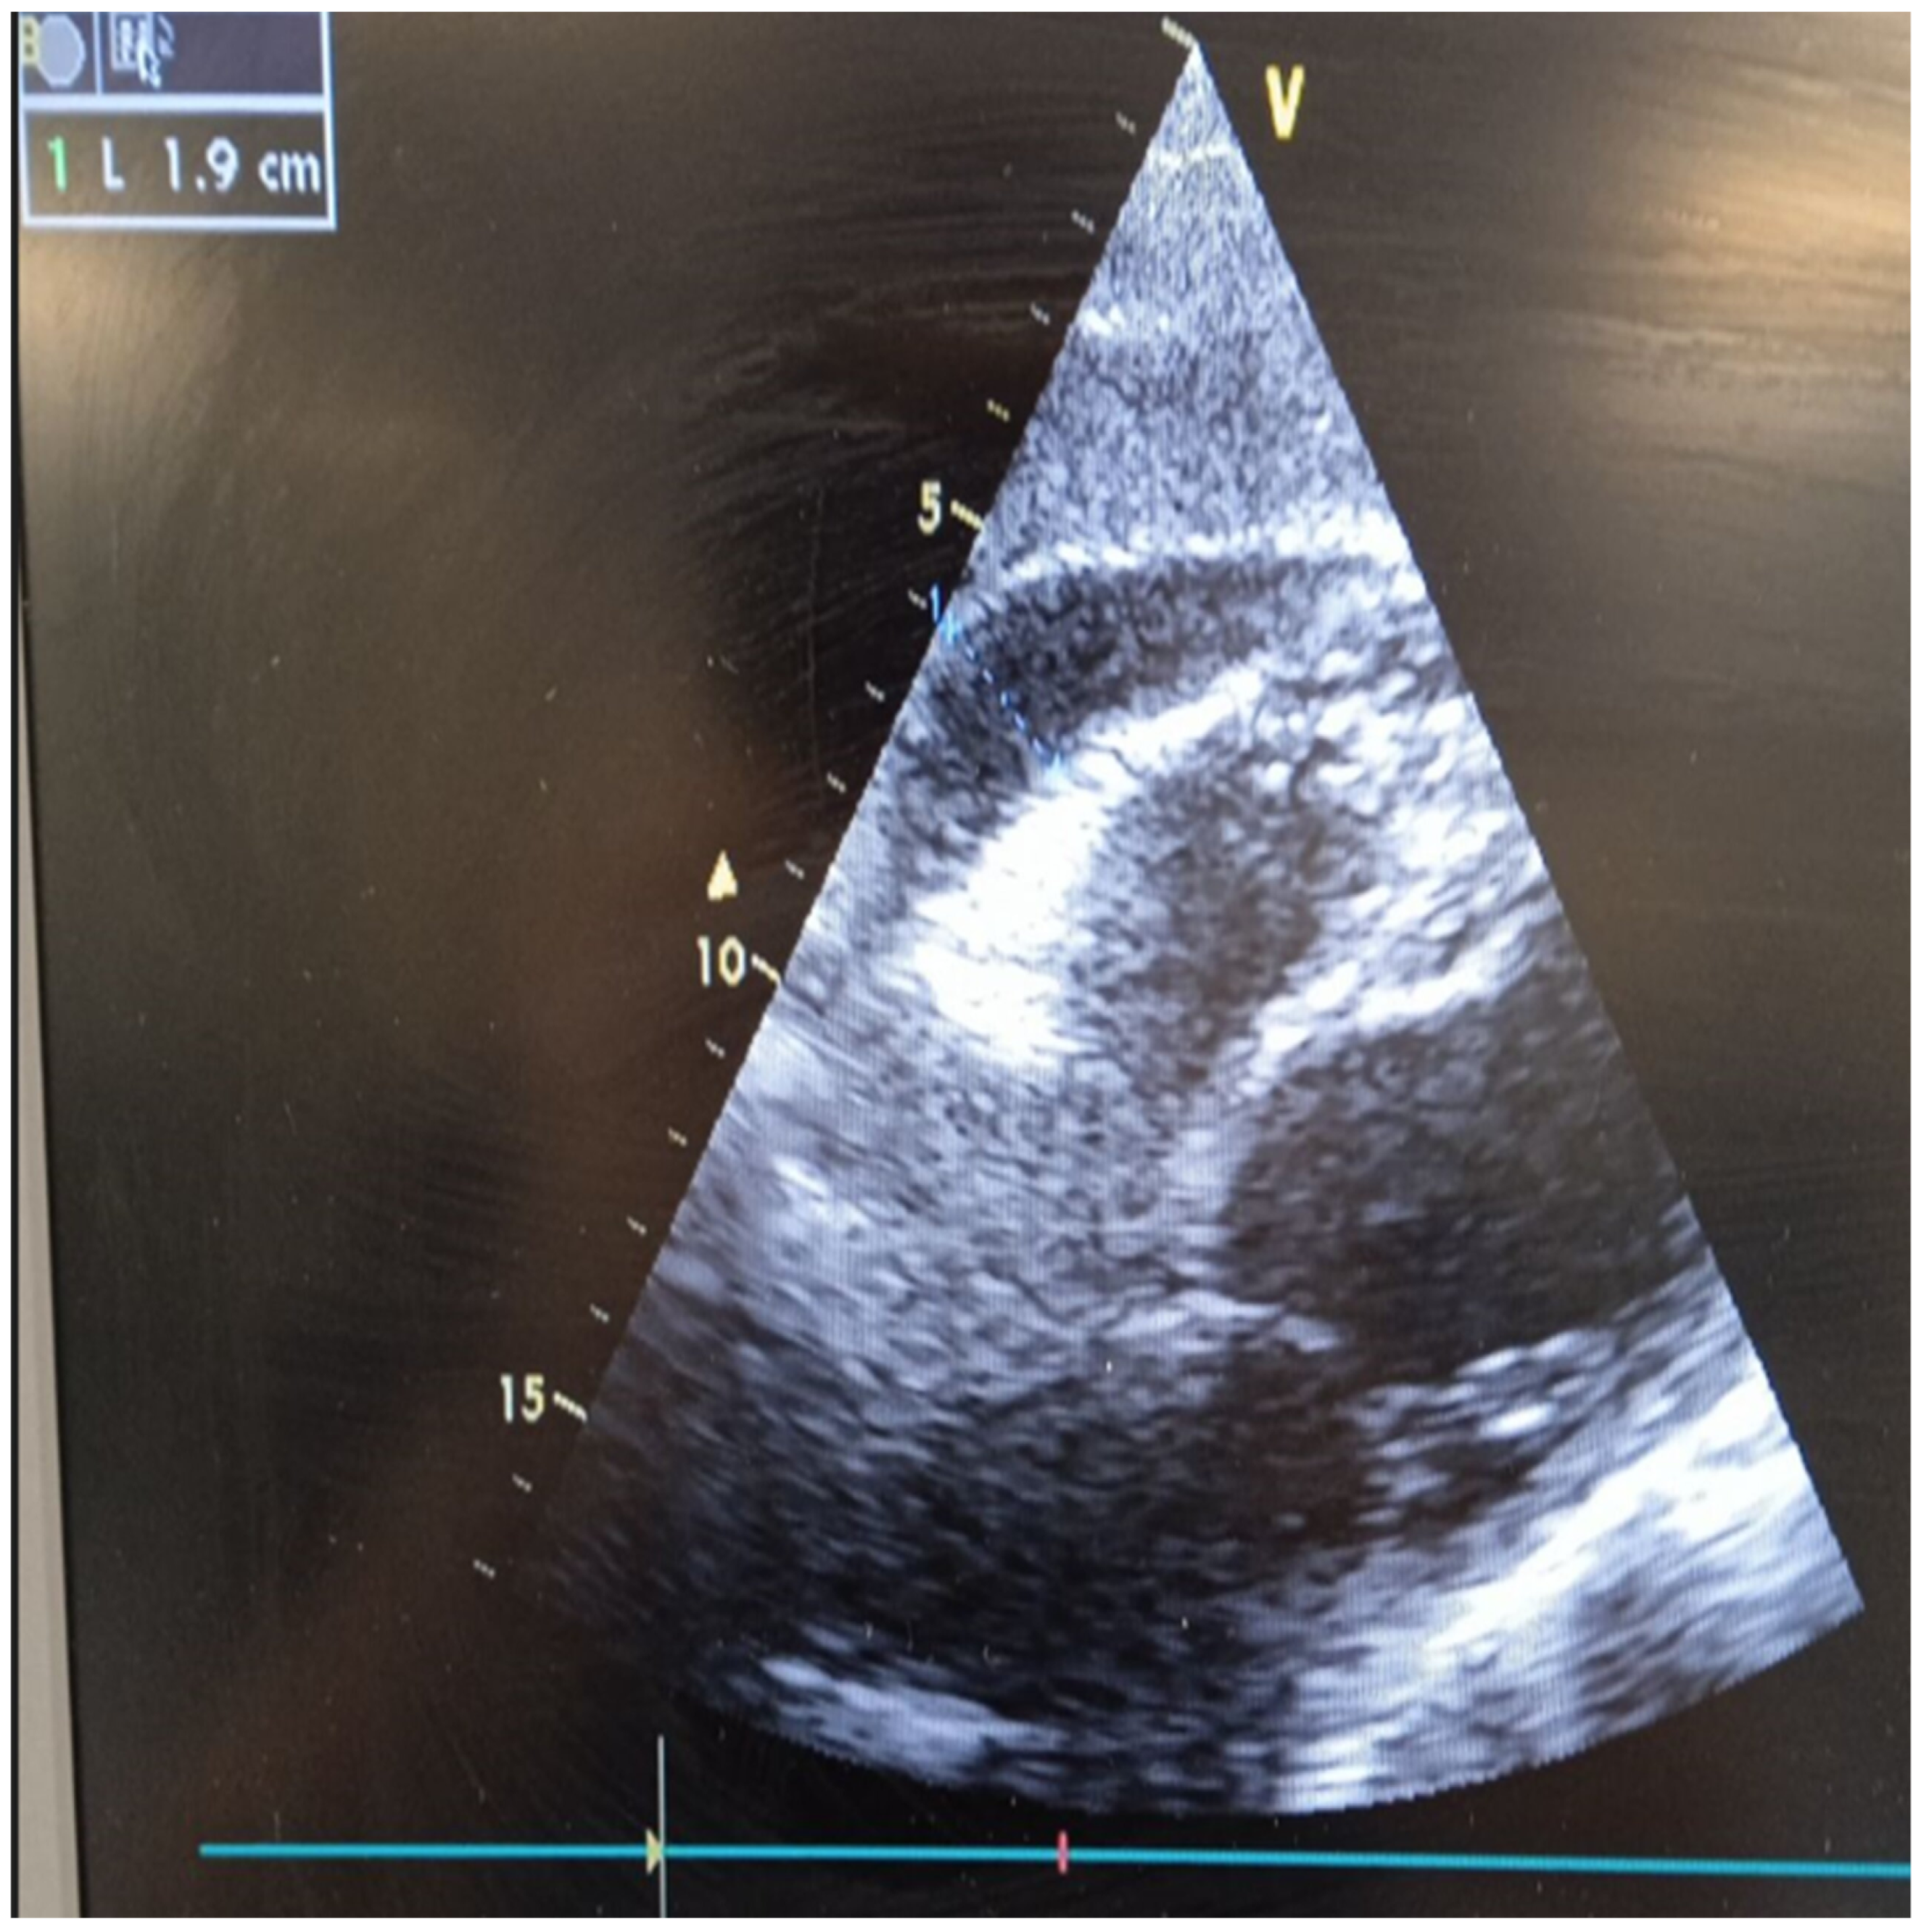

2. Case Report